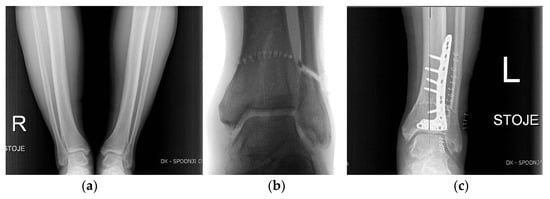

4.7. Ankle and Foot

5.7. Ankle and Foot